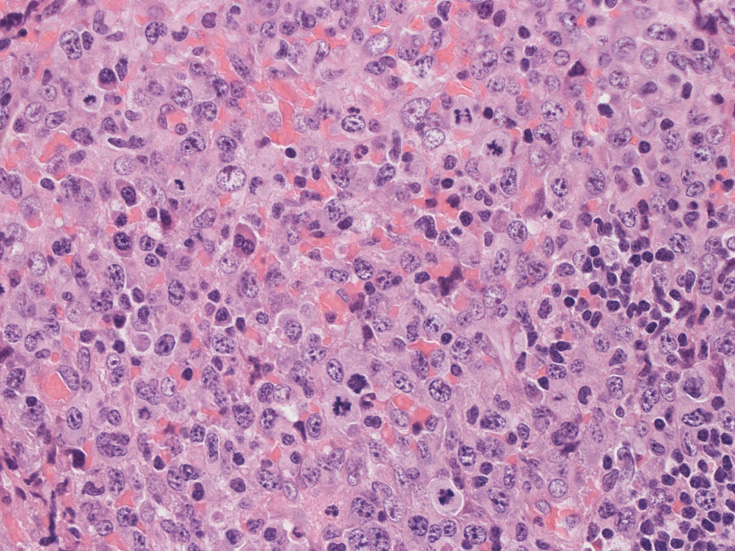

高倍率x400では, 増殖細胞はcentroblastに似て複数の明瞭な核小体をもった淡明な大型類円ないし卵円形核を持っている。核分裂像が多い。この症例では多型はめだたない。典型的な腎臓型のくびれた核を持つ細胞などはない。ALKの形態的variant症例と考えられるが, 化学療法後の再発による影響も否定できない。

腫瘍細胞x400細胞質の豊富な異型細胞核分裂が多いx400